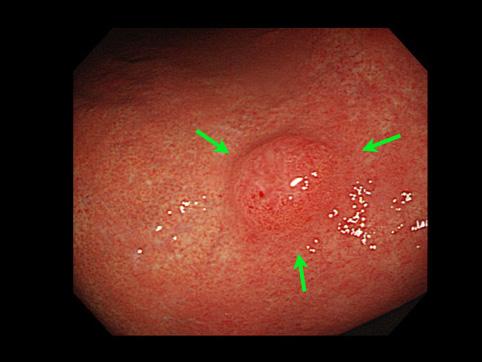

Pólipo Hiperplástico del Estómago con la formación de irregularidad superficial como de pulpo

Lesión que asemeja tumoración/Pólipo Hiperplásico

estómago(región)/mas de dos

diámetro mayor del tumor

10 - 14